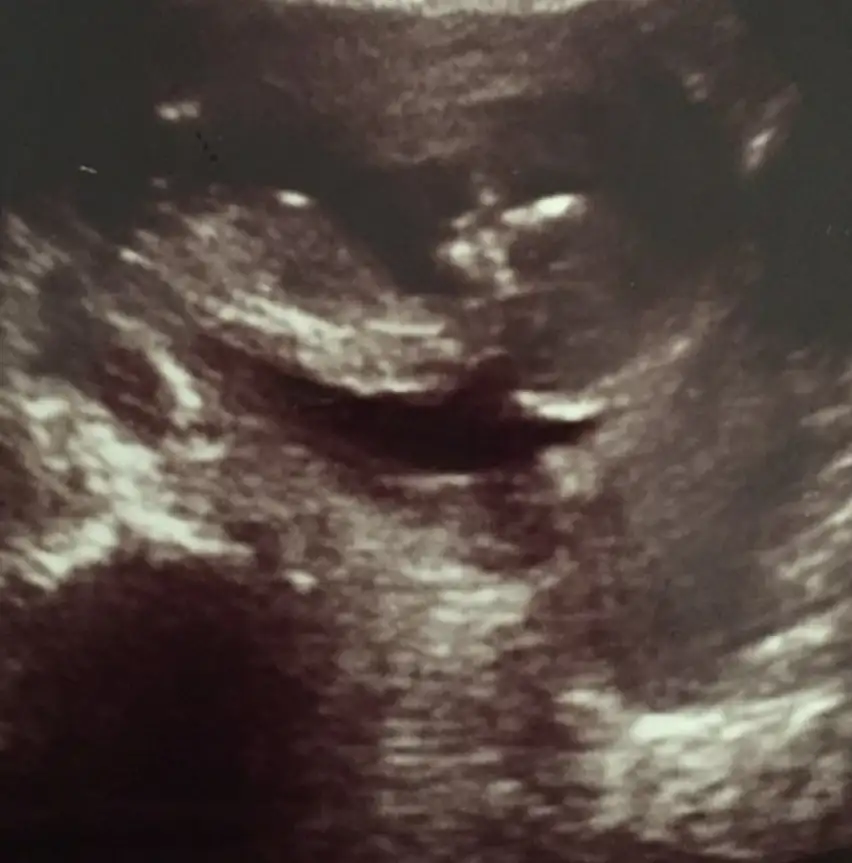

Bir tomurcuk var sanki erkek olabilir yinede USG istiyorum net değil birde 11 hafta değil sanirimBiseye benzetemedim

Erkek gibi ama tekrar USG istiyorumSelamIkra meyra banada yorum yapabilirmisin 11+3 teyiz Ikra meyra

Gerçekten kaç haftalıkmış ikracım bu bebişYok nuba iyi bakarsan dik ve parlak cnm Dr da erkek demis